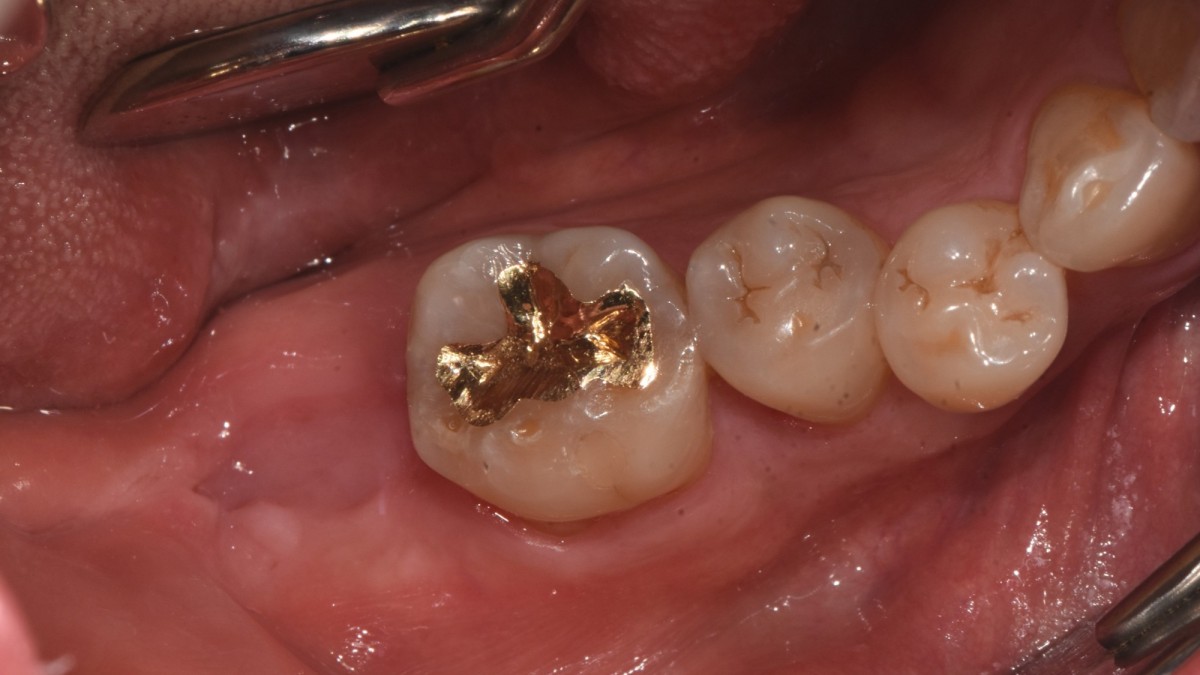

A 47-year-old male patient had a crown with an ill-fitting margin and crack-tooth syndrome in the lower 2nd molar. No systemic issue.